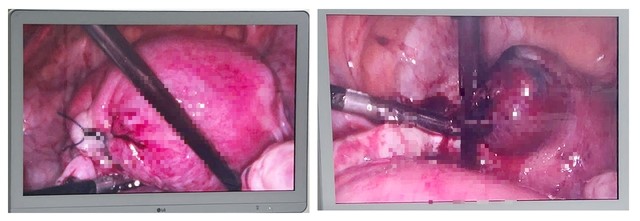

Cứu sống sản phụ mang song thai ngoài tử cung, sốc mất máu

Thứ Năm, ngày 08/05/2025 01:30Bệnh viện Việt Nam – Thụy Điển Uông Bí (Quảng Ninh) vừa phẫu thuật thành công, cứu sống một phụ nữ 36 tuổi mang song thai, chửa ngoài tử cung bị sốc mất máu. Thời điểm vào viện, bệnh nhân...